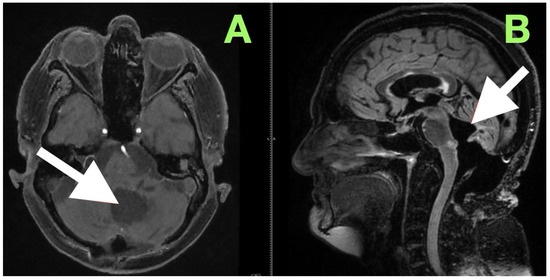

Background and Clinical Significance: Fourth ventricular epidermoid cysts are among the least frequently encountered intracranial tumors (less than 1%). Their slow growth pattern along cisternal and subarachnoid spaces, and their close proximity to neurovascular structures (brainstem–cerebellar), create difficulty for surgical treatment. Total [...] Read more.

Background and Clinical Significance: Fourth ventricular epidermoid cysts are among the least frequently encountered intracranial tumors (less than 1%). Their slow growth pattern along cisternal and subarachnoid spaces, and their close proximity to neurovascular structures (brainstem–cerebellar), create difficulty for surgical treatment. Total removal is often complicated by the capsule’s adherence to eloquent structures and requires a thoughtful surgical approach of weighing radical resection versus neurologic/function preservation. This case description provides an example of using careful clinical–radiological correlation and anatomy-dissecting microsurgery as a method of permanent decompression and neurologic recovery with low operative risk. Case Presentation: A 57-year-old female presented with impaired stability of gait, gaze-evoked nystagmus, appendicular ataxia, minimal ipsilateral hypotonia, and mild bulbar dyscoordination. Imaging (MRI, MRA) revealed a large, lobulated mass that was lobulated and avascular centered in the left cerebellar hemisphere, with an extension into the vermis and cisterna magna, and partial filling of the fourth ventricle with classic epidermoid imaging. Resection was performed via a midline suboccipital telovelar approach with microsurgery, relying on native arachnoid planes and quadrant opportunities of decompression, while preserving critical neurovascular structures. A thin rim of capsule intimately adherent to the floor of the ventricle was intentionally left to minimize irreversible cranial nerve injury. Histology showed keratinizing stratified squamous epithelium with laminated keratin and cholesterol clefts. Following resection, truncal stability, limb coordination, and ocular pursuit improved without additional deficits. Initial and 3-month postoperative MRI showed total decompression, re-established CSF pathways, and no recurrence. Conclusions: This case demonstrates that maximal safe resection (with function preservation) through natural anatomy corridors can achieve excellent neurologic results in fourth ventricular epidermoids. Lifelong MRI surveillance will be needed due to the srisk of delayed recurrence even after near-total resection. Full article